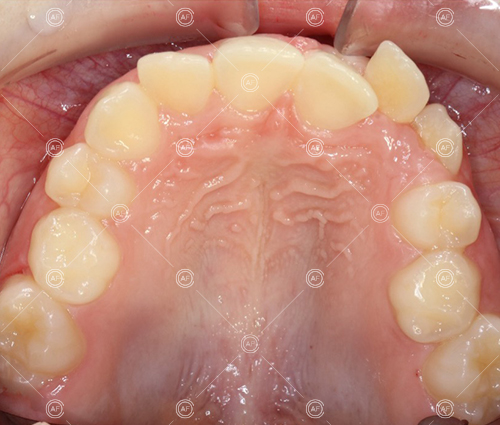

This patient (MH) began her active orthodontic treatment in October 2019 at almost 13 years old. She was unhappy with the appearance of her upper and lower teeth, and especially concerned about the unsightly nature of the high and buccally positioned upper left canine.

about this case…MH presented with class 1 incisors on the class 1 skeletal base with a slightly increased vertical proportion. She had severe crowding in the upper arch and moderate crowding in the lower. Due to the crowding in the lower arch, the lower centre line was off to the left by 2mm.

Buccal segments were essentially class 1 on the right hand side and a full unit class 2 on the left. This is due to buccal exclusion of the upper left 3 and mesial drift of the upper buccal segment.